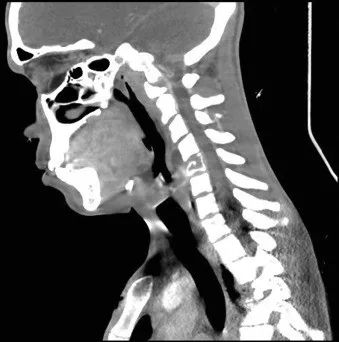

全血白细胞计数为13.4*109/L,血红蛋白8.5g/dL,血小板138/μL,C-反应蛋白28.8(正常值<3.0)。动脉血气分析显示pH值为7.30,PCO2为48.2,PO2为71.8,血培养呈阴性,进行BAL培养(包括细菌培养、病毒培养、真菌培养)。胸部X线及胸部CT显示弥漫性斑片状阴影(图1.2)。颈椎、胸椎和腰椎的CT扫描显示椎体病变(图3.4)。由于脾脏有多处病变,也进行了脾活检(图5)。

图3 颈椎/胸椎CT:C5椎体广泛透明、前路高度破坏约70%